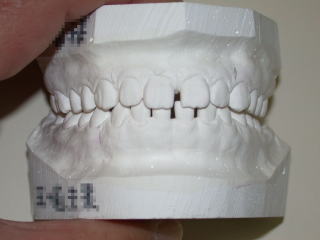

術後を予測するセットアップモデル。

平成26年8月8日